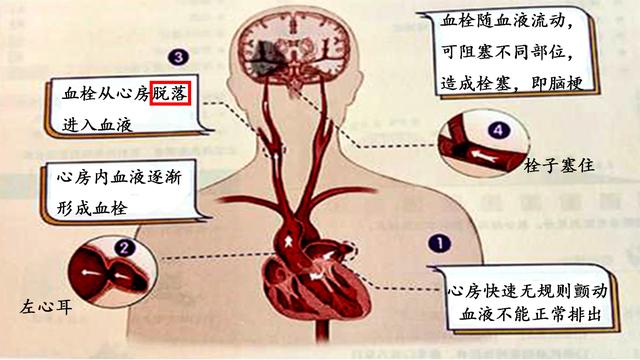

脳梗塞の原因としては、よく耳にする心房細動もあるが、心房内に塞栓ができると、それが外れて脳梗塞になることがある。したがって、心房細動も脳梗塞の重要な原因である。もちろん、心房細動による脳梗塞と脳動脈硬化症や脳血栓症による脳梗塞とは病態基盤が全く異なるので、通常の治療法も異なり、抗血小板療法を強化する場合と、抗凝固療法に注意する場合とがある。

4、一目で答えの比較は、ここで少し拡大するように、脳塞栓症は、多くの場合、心機能の問題を伴っている、臨床我々は、脳塞栓症患者は、多くの場合、心房細動を伴うことがわかった、この異常な心拍パターンは、多くの場合、脳塞栓症をもたらす脳に到達する体の血液循環で、血栓オフの心臓の壁に取り付けられている。

5、心房細動患者に対して、我々は積極的に心房細動による害を予防しなければならない、心房細動患者の脳血管リスクは普通の人より約60%高い、どのように心房細動に介入するか、古い治療方法であるワルファリン薬の使用(弊害は出血のリスクが増加することで、定期的に病院に行って凝固機能を見直す)、現在では新しいタイプの抗凝固薬(例えば:ダビガトランやリバロキサバンドロン薬)を使用する傾向があり、安全性ははるかに優れています。現在では、より安全性の高い新しい抗凝固薬(例えば、ダビガトランやリバロキサバンドロン)が使用されることが多くなっています。

脳塞栓症を心臓性脳塞栓症と呼ぶ人もいるが、これは脳塞栓症の一般的な原因が心臓にあり、心臓の異常病変が塞栓を生じやすいことを示している。心房細動、リウマチ性心疾患、急性心筋梗塞、人工心臓弁などである。

大別すると、脳梗塞の原因となる血栓には、プラークが破裂して血栓を形成する動脈硬化が大部分を占める場合と、心筋梗塞の不整脈である心房細動によって形成される血栓の2種類がある。

また、不整脈の心房細動によってできる血栓もある。正常な心臓では、拍動のたびに心臓内の血液がすべて送り出され、心臓内に血液が残留することはない。しかし、心房細動が起こると、血流の一部が心臓内に滞留し、血液が長時間滞留すると、血液が固まって血栓(血の塊)を形成する。そして、この血栓が血管とともに脳血管に流れ込み、脳血管を閉塞して脳梗塞を引き起こす。このような脳梗塞を防ぐには、心房細動が発見されたら、抗凝固療法、心房細動を治す手術、左耳の閉塞など、どのようなものであっても、専門医を見つけ、専門的な治療を受け、正式に治療することである。